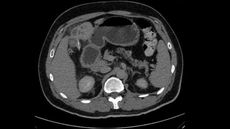

Diagnostic dilemma: A man who couldn't pee had been infected by one of the largest known human parasitesA 35-year-old man who couldn't pass urine learned that the cause of his obstruction was a giant worm living in his kidney.